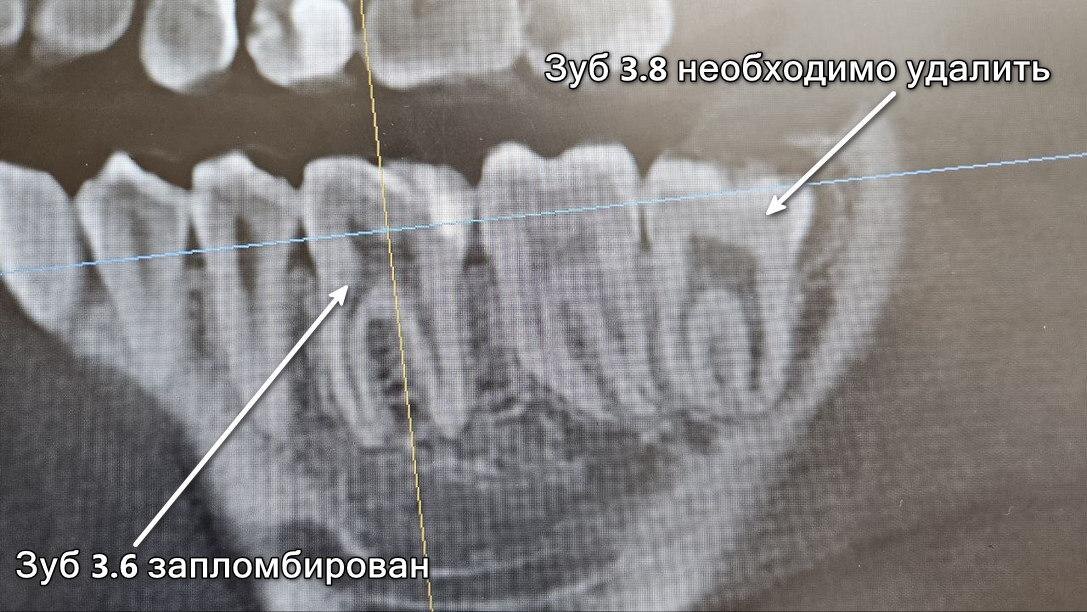

Снимок до удаления зуба 3.8

Оксану беспокоил зуб 3.8. Периодически у нее отекала щека, было больно пережевывать пищу, восьмерка «давила» на десну. Боль доставляла дискомфорт в течение нескольких дней, потом проходила и девушка забывала об этом на время. Ничего необычного — зуб мудрости удалили без осложнений.

Через месяц Оксана вернулась в клинику для осмотра после хирургической процедуры. Причиной визита была боль в области удаленного зуба, которая появляется, несмотря на быстрое и заживление. Снимок, сделанный через месяц после предыдущего, вызвал удивление у нескольких врачей. На нем огромная киста корней зуба 3.6, которой до этого не было. Дискомфорт в области удаленного зуба — это иррадиирующая боль от зуба 3.6😱